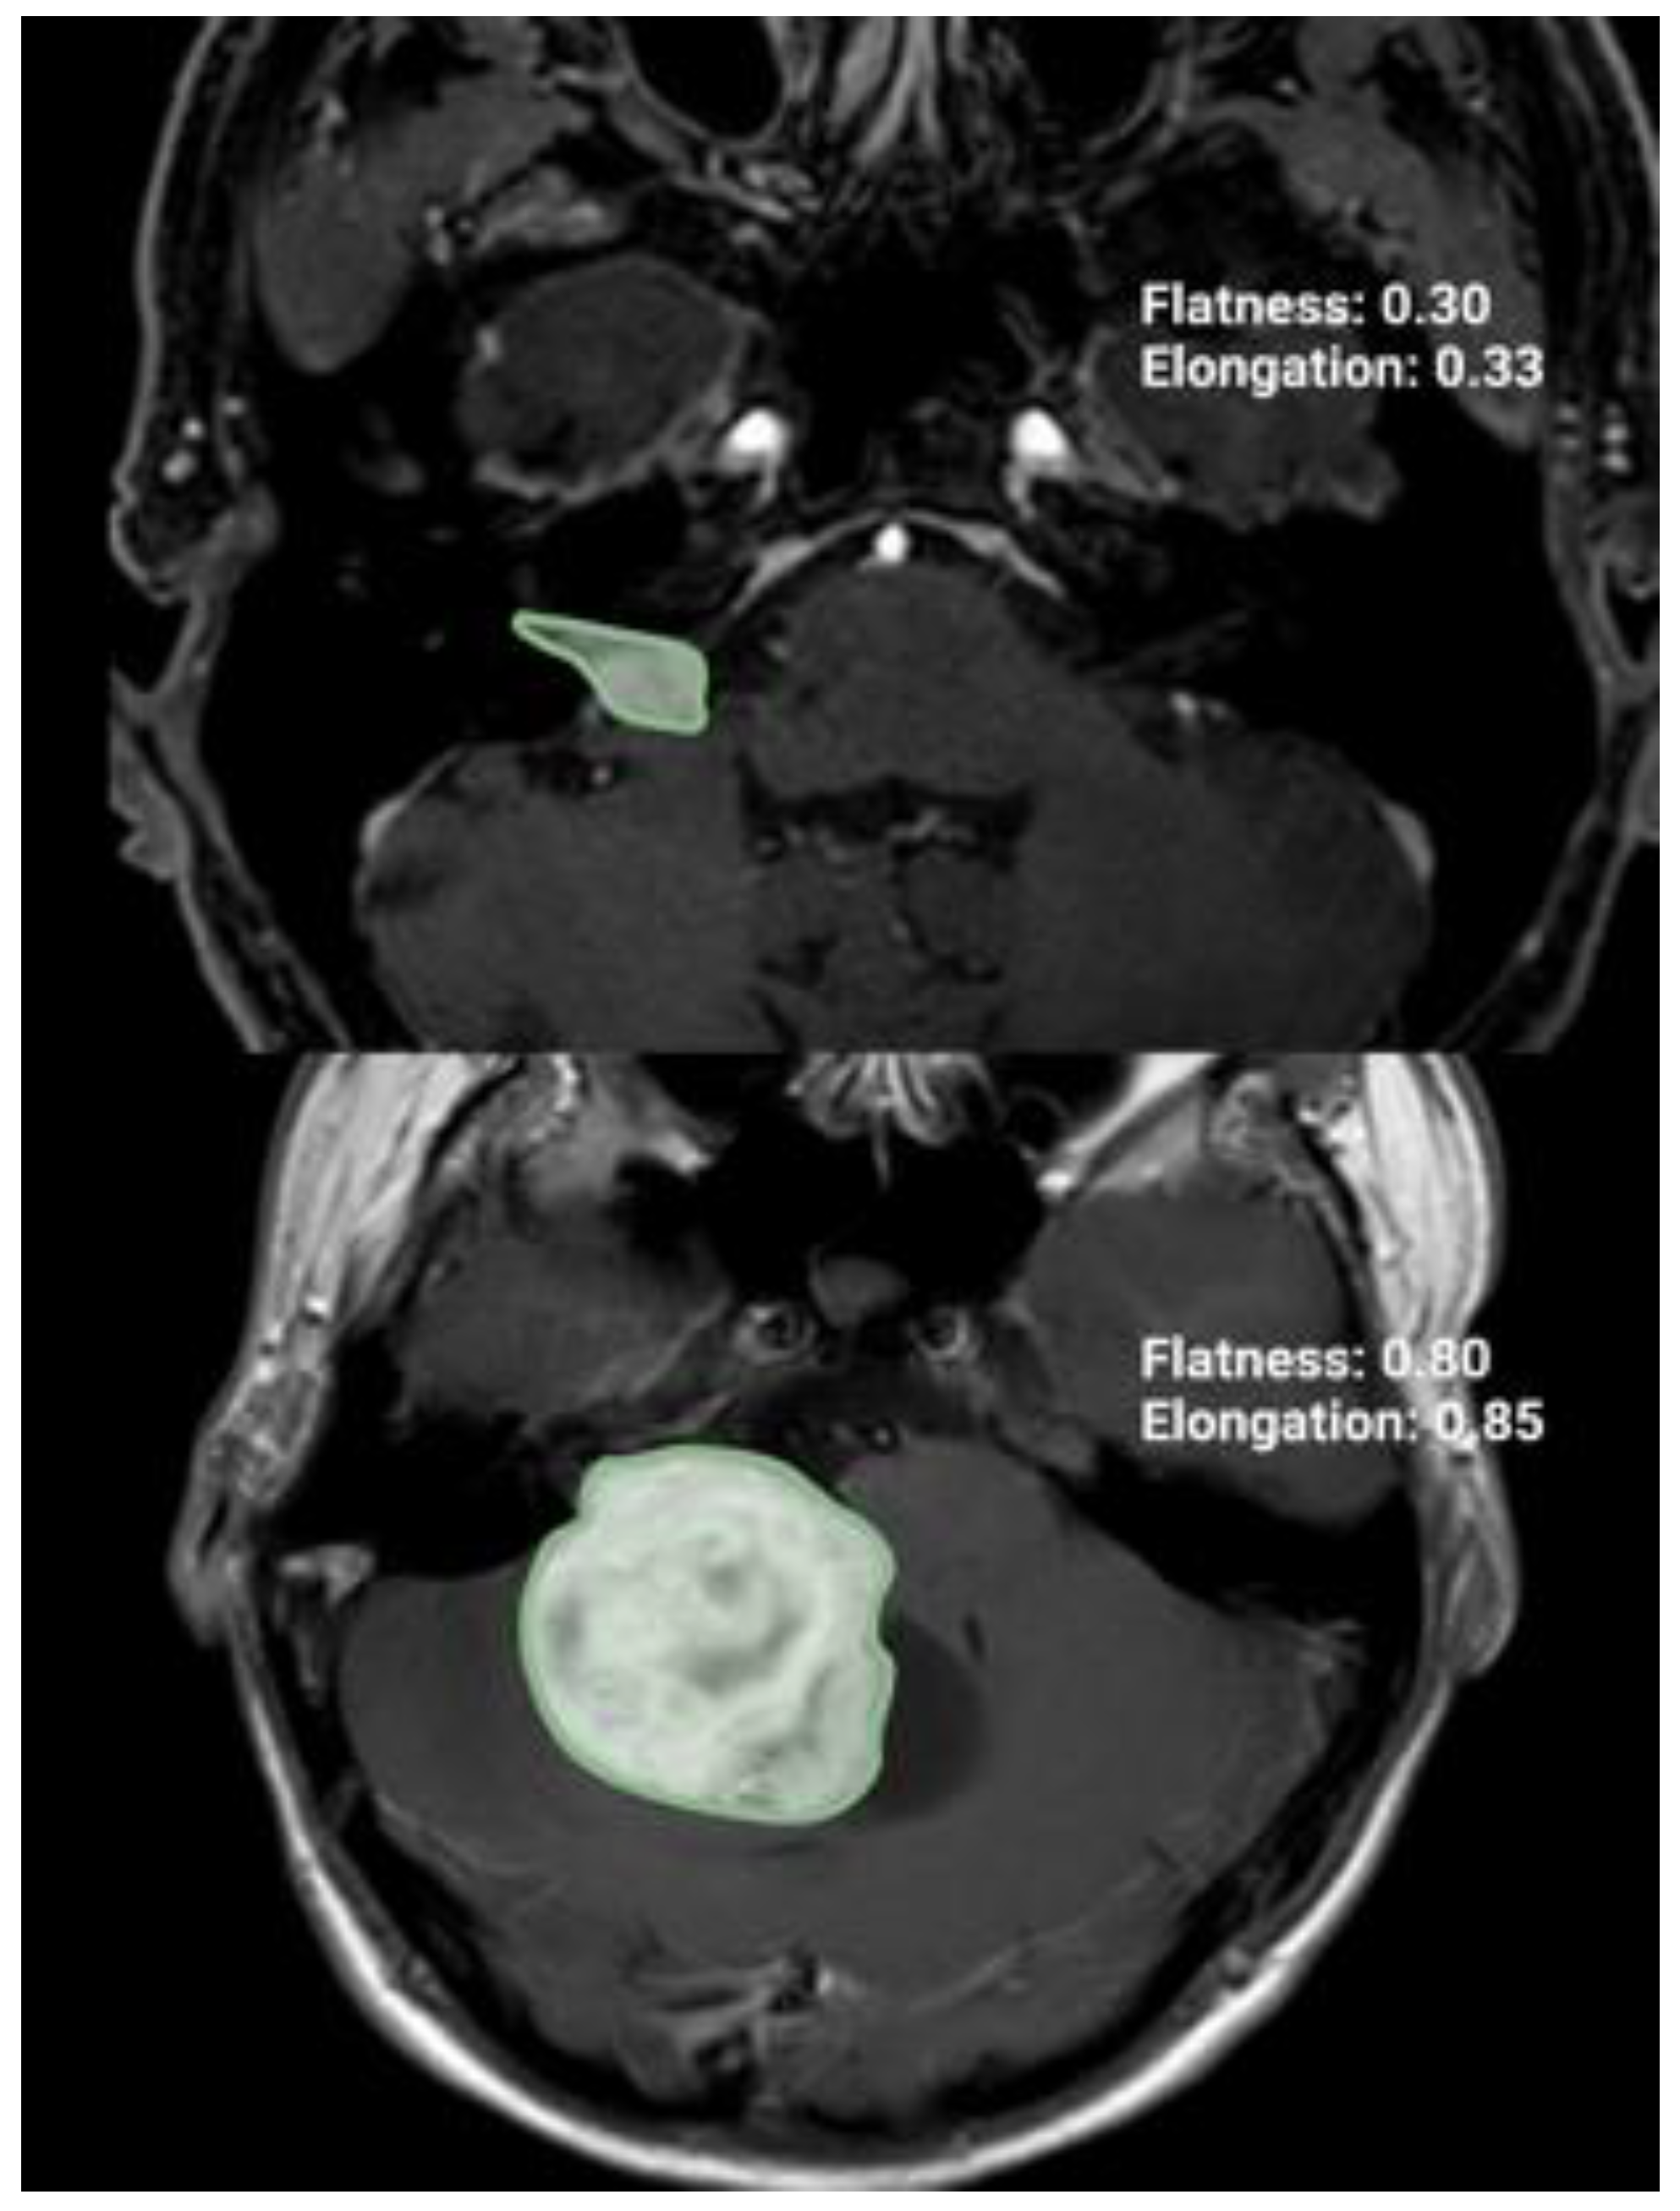

GTR refers to the complete removal of the tumor, while NTR, STR, and partial resections PR are defined as removing more than 90–100%, 80–90%, and 80% or less of the initial preoperative tumor volume, respectively []. Through these MR images, the pre- and postoperative tumor volumes, surface area, extent of resection (%), and radiomic tumor shape features (elongation, flatness, sphericity) were calculated by using volumetric analysis in a 3D slicer software (version 5.4.0, Surgical Planning Laboratory, Harvard University, Cambridge, MA, USA). The tumor was independently identified by two individuals with a neurosurgery background. Three-dimensional models were constructed using the tumor outlines to determine the VS volume and VS surface area with the “Fast Marching” method in a 3D slicer software (version 5.4.0.; https://www.slicer.org (accessed on 24 November 2023)) []. The tumor shape was quantified using elongation (see Figure 1). The elongation is calculated from the square root of the ratio of the second largest principal moment to the second smallest: [].

Figure 1.

Illustration of two axial T1-Gd-enhanced MR images representing two cases with different radiomic shape parameter elongation.